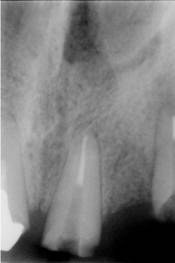

La nivelul lui 21 se observa obturatia de canal corect executata din punct de vedere radiologic. Clinic se constata obturarea canalului radicular cu ciment oxifosfat de zinc si fara con de gutaperca. Pe a doua radiografie se observa dezobturarea corecta a canalului radicular pt. realizarea unui DCR